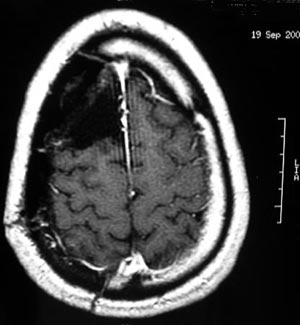

Figura 95- Ressonância nuclear magnética pós operatória revelando a ressecção da lesão. A paciente evoluiu com diminuição de força na metade esquerda do corpo (hemiparesia esquerda). Em 2 semanas voltou a caminhar sozinha. Houve melhora importante das crises.

Figura 99 - Ressonância nuclear magnética pós-operatória revelando a ressecção. Apresentou apenas 1 crise fraca em 2 anos de seguimento depois da cirurgia quando tentou-se retirar a medicação anticonvulsivante.